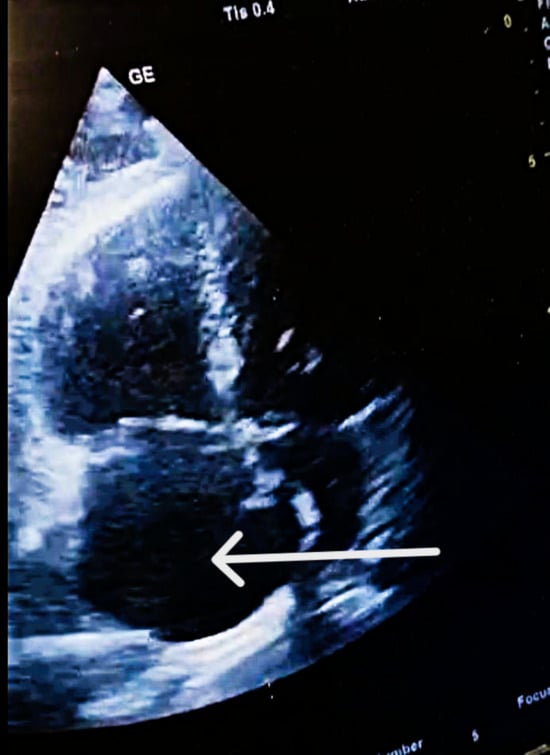

| Mobile RA thrombus | Large, serpentine, prolapsing through tricuspid | High embolic risk |

| Thrombus mobility | Free-floating, unstable | High embolization potential |

| Interventricular septum | Paradoxical motion | “D-shaped” LV; RV overload |

| RV diameter | 46 mm (below tricuspid/pulmonary annulus) | Marked RV dilation |

| LV diameter | 33 mm | Normal size |

| RV/LV ratio | >1 | Consistent with acute RV pressure overload |